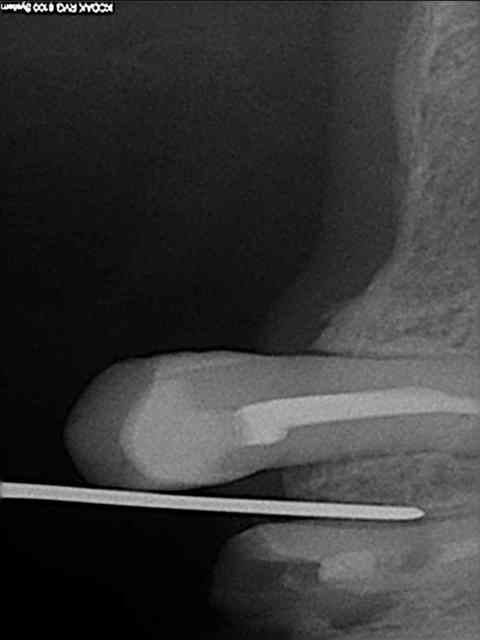

aussitôt demandé, aussitôt fait !!

(j+1 an)